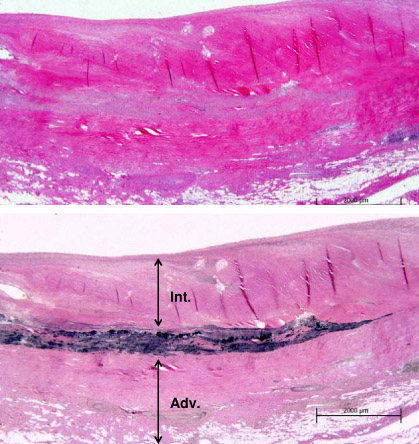

The immunological and inflammatory response seen in arteries is similar to that observed in large arteries in giant cell arteritis.[1][4] During the acute phase of vasculitis, inflammation begins in the vasa vasora of the adventitia of muscular arteries.[1][9] T cells are prominent in the initial cellular response, and anti-endothelial cell antibodies may also be involved.[1][4][21][22][Figure caption and citation for the preceding image starts]: Photomicrograph of the aorta from a patient with Takayasu's arteritis demonstrates marked thickening of the intimal layer and inflammatory infiltrates in the media and laminar necrosisUsed with permission from the collection of Dylan Miller, MD, Mayo Clinic [Citation ends].